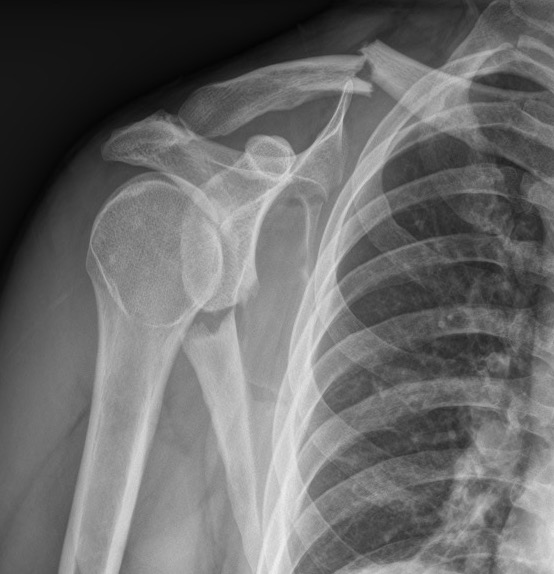

Glenoid fracture + lateral clavicle fracture + acromial fracture